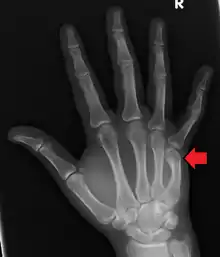

Boxer's fracture of the 5th metacarpal head from punching a wall

A boxer's fracture is the break of the 5th metacarpal bones of the hand near the knuckle.[4] Occasionally it is used to refer to fractures of the 4th metacarpal as well.[1] Symptoms include pain and a depressed knuckle.[2]

Classically, it occurs after a person hits an object with a closed fist.[3] The knuckle is then bent towards the palm of the hand.[3] Diagnosis is generally suspected based on symptoms and confirmed with X-rays.[3]

Diagnosis by a doctor's examination is the most common, often confirmed by x-rays. X-ray is used to display the fracture and the angulations of the fracture. A CT scan may be done in very rare cases to provide a more detailed picture.